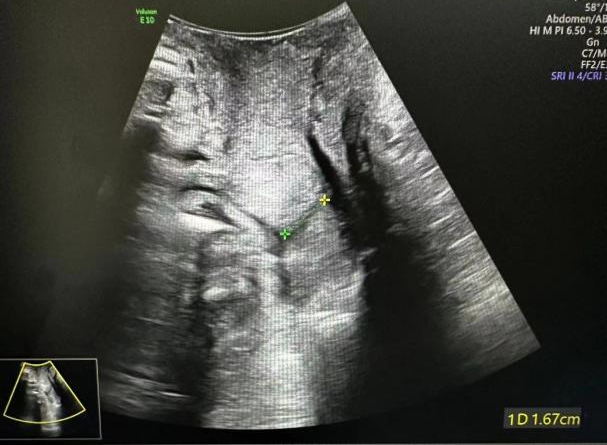

术前宫颈有效长度1.67cm

术后有效宫颈长约2.4cm